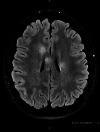

Viral infections can serve as a trigger for variable autoimmune, antibody-mediated demyelinating disorders. There is accumulating evidence that the severe acute respiratory syndrome coronavirus 2 (SARS-CoV-2) virus, causing coronavirus disease 2019 (COVID-19) infection and responsible for the current worldwide pandemic, can lead to a cascade of immune-mediated brain and spinal cord demyelinating injuries. However, such observation in the pediatric age group was only reported in very few patients. Thus, the heterogeneous spectrum of this phenomenon in children is still unfolding. We are reporting a case series of five pediatric patients with a variety of acute central nervous system (CNS) demyelinating disorders in the context of acute or recent COVID-19 infection. A 16-year-old female with anti-myelin oligodendrocyte glycoprotein (MOG) disorder, an eight-year-old male with acute disseminated encephalomyelitis (ADEM), a 13-year-old female with neuromyelitis optica spectrum disorder (NMOSD), and two 14 and 13-year-old females with new-onset multiple sclerosis (MS) are reported, all of whom presented acutely following COVID-19 infection. We propose that para and post-infectious CNS demyelinating disorders can potentially follow acute COVID-19 infection in children. Considering SARS-CoV-2 testing as a part of diagnostic workup is possibly useful. Awareness of the presence of this phenomenon can help in the recognition and management of those patients.